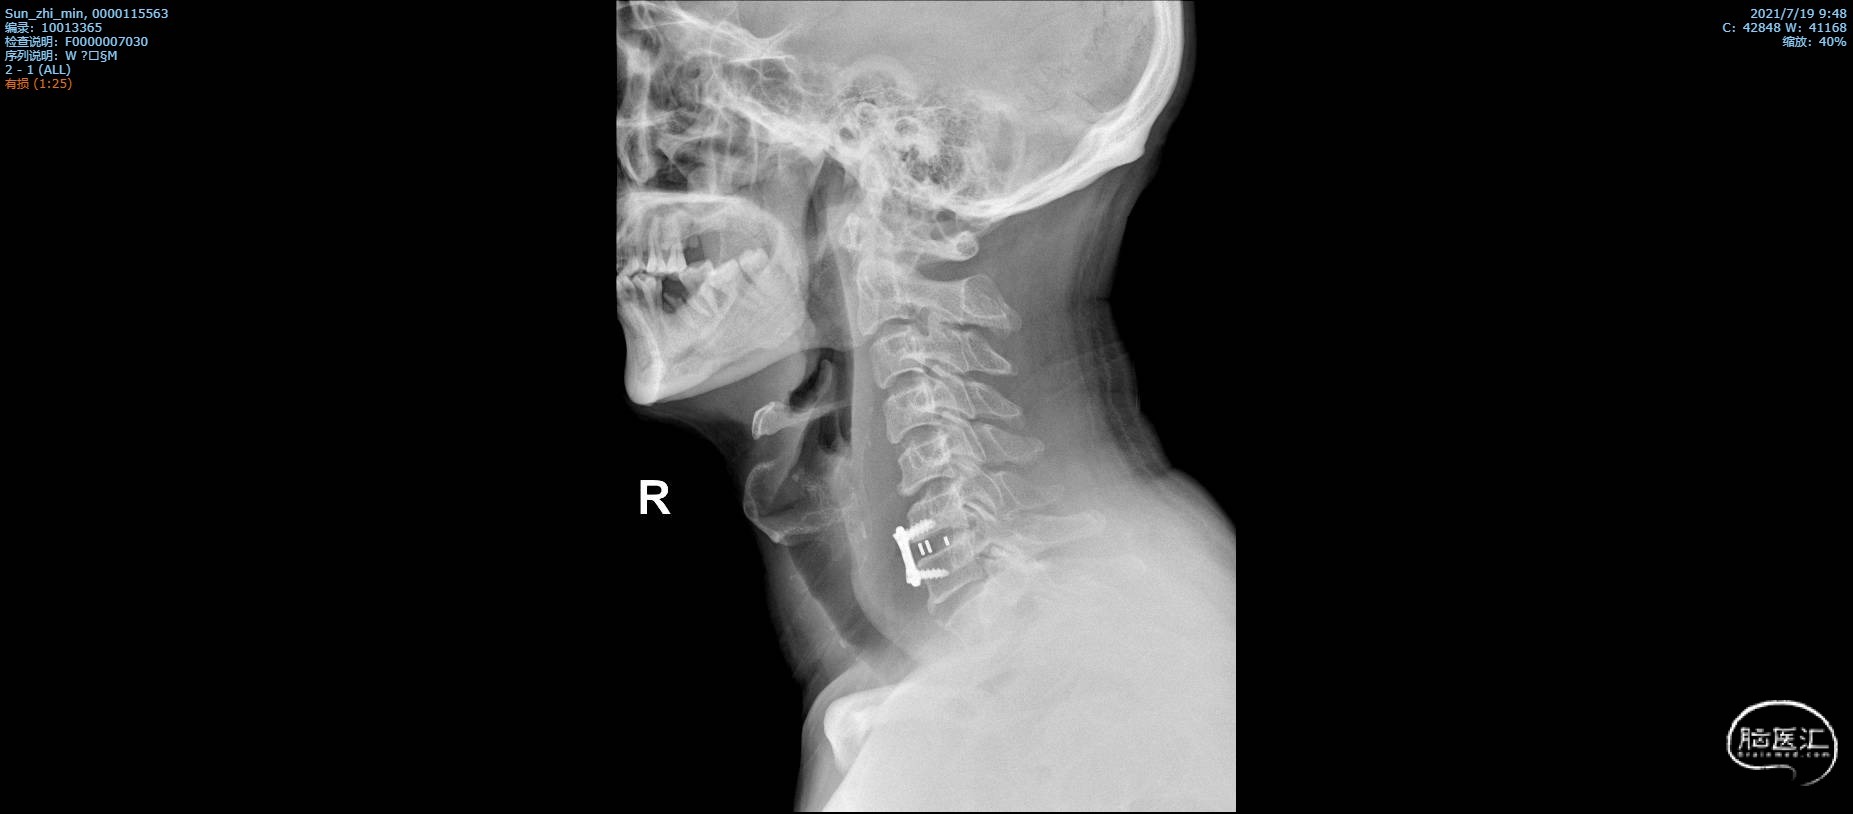

术后颈椎X线片复查

X线正位

X线侧位